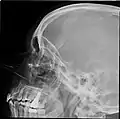

Paranasal sinuses

Lateral projection of the paranasal sinuses